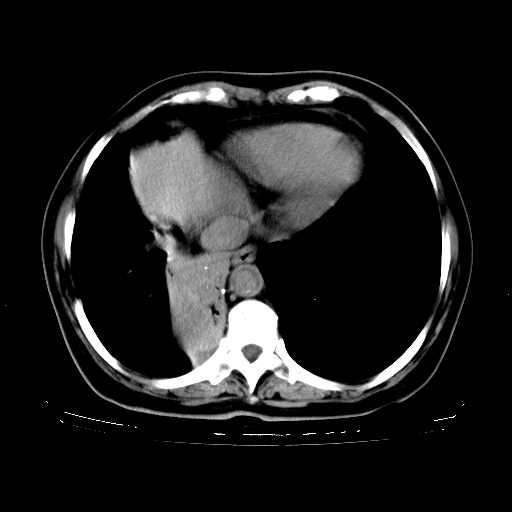

标题: CT23067:女,70岁,咳嗽、咳痰一个月,低热一周。 [打印本页]

女,70岁,咳嗽、咳痰一个月,低热一周。

1.左上肺结核,部分纤维化。右肺中下叶部分肺不张,内见液化、坏死及点状钙化,右中下叶支气管壁增厚、管腔狭窄,见多个点状钙化,结合临床考虑支气管内膜结核,建议痰检查抗酸杆菌并参考血沉。两肺多个小圆点状高密度灶,境界模糊,多考虑结核肺内播散。但本人年龄较大首先应支气管镜检以除外右肺癌。

2.胸主动脉夹层。